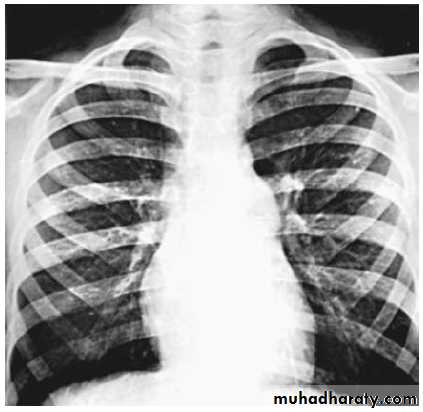

CXR:

the heart size is usually normal (but may shows cardiac enlargement with prominence of the right ventricle and right atrium).

the main PA segment may be prominent because of poststenotic dilation of the main pulmonary artery.

PS: normal heart size but post stenotic dilation of PA